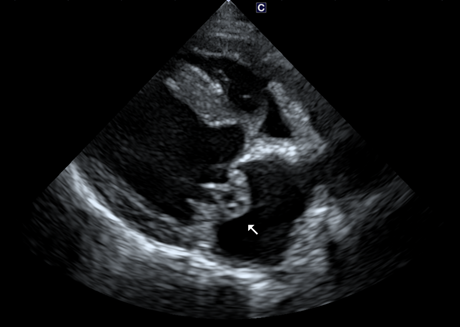

심장 초음파 보겠습니다

판막의 심한 변성과 Prolapse가 존재합니다.(화살표 모양)

좌심방의 크기를 나타내는 LA:AO는 1.79가 나왔습니다(정상은 1:1입니다)

좌심방의 압력을 간접적으로 나타내는 E vel은 많이 낮아졌습니다.

(보통 1.5m/s가 넘으면 폐부종이 터진 상황이거나 터지기 직전 상황입니다)